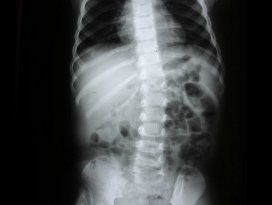

Omurga eğriliğine dikkat